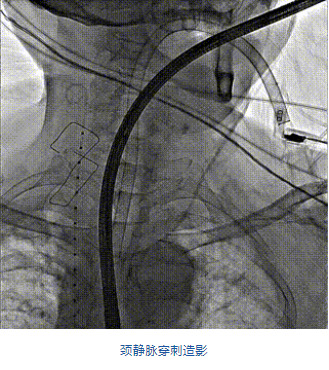

團(tuán)隊(duì)前期經(jīng)過多次討論,制定了周密的手術(shù)策略和預(yù)案。由于患者已是近九旬的超高齡老人,傳統(tǒng)外科開胸手術(shù)風(fēng)險(xiǎn)極高,純介入經(jīng)血管三尖瓣替換能夠明顯減少創(chuàng)傷。術(shù)中陳茂及馮沅教授結(jié)合體表定位在造影指示下精準(zhǔn)穿刺右側(cè)頸靜脈并預(yù)置兩把血管縫合器。成功建立經(jīng)皮血管入路后在食道超聲和DSA的引導(dǎo)下順利完成人工瓣膜植入,術(shù)后超聲和造影顯示人工三尖瓣同軸性良好,瓣架固定牢靠,無反流和瓣周漏,平均跨瓣壓差降為1mmHg。術(shù)畢收緊預(yù)置的血管縫合器縫線完成止血,縫合效果滿意,在手術(shù)室即刻拔除氣管插管。